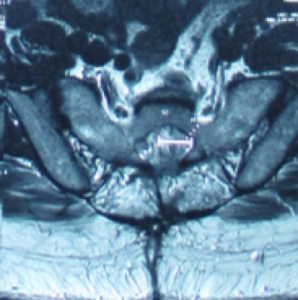

Tarlov cyst generally find at the first to the third section of the sacrum and is filled with cerebrospinal fluid. The swelling can gradually increase and cause the cauda equina nerve to be compressed, causing nerve root inflammation or myelopathy and even affecting the bony structures. Magnetic resonance imaging can clearly distinguish the location, size, and relationship with the dura and nerve roots of the sacral canal.